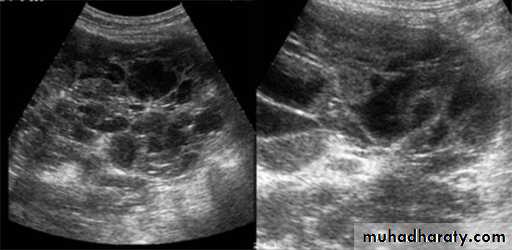

Polycystic renal disease in ultrasound demonstrate numerous cysts seen in cortex & medulla